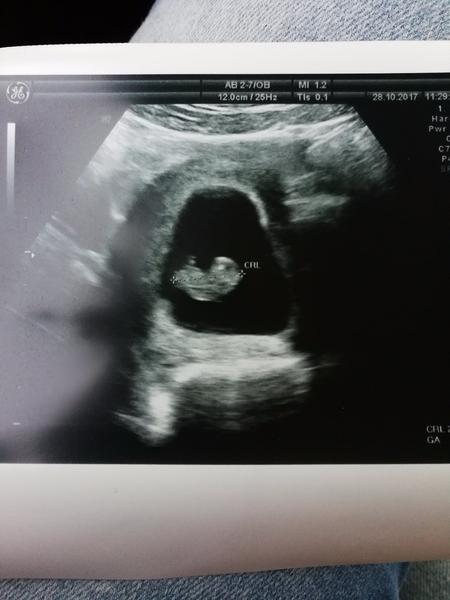

Kedy si toto bol moj dusis teraz je to mala princezna ktora o chvilku bude medzi nami .Verim ze vsetko dopadne tak ako ma .Uz len chvilky a budem ta dzat v naruci .Tvoj velky brat , tatino,babi a ja sa tesim velmi na teba srdiecko nase milujeme ta uz teraz😚😙😍😘😗 ....prepacte mala som ten pocit napisat moje pocity v tomto momente 😊☺